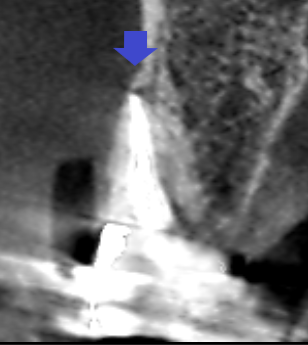

上顎第一大臼歯の近心頬側根の冠状断のCT画像です。

矢印の先の上顎第一大臼歯の近心根に膿の影がみられます。根管充填は根の先まで届いていますが、膿ができていました。